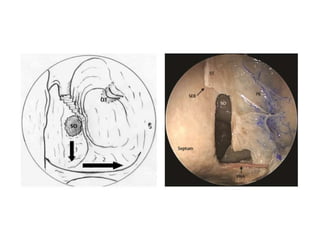

B. Management of Middle Turbinate

 The anatomical variants of the middle

turbinate may cause middle meatal

obstruction like Choncha Bullosa where the

head of MT is enlarged.

 Resection of CB is done by incising the

inferior free border of MT along its length

and carrying the incision up to the neck.

The incision is further enlarged using

microscisor & the lateral half of the concha

is removed after elevating the mucosal flap

from the lateral bony wall